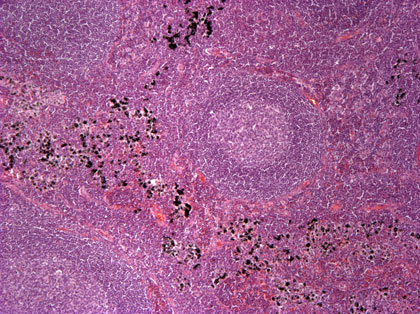

Lymfknuta med antrakos, översikt |

Lymfknuta med antrakos

Stark inlagring av kolpartiklar i lymfknutans makrofager. Resten av lymfknutan är fylld av normala lymfatiska celler.

40x, H&E.